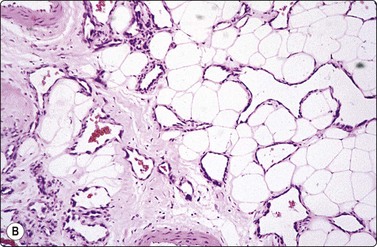

Fat necrosis (Fig. 7.19)

image image image

Fig. 7.19 Fat necrosis

(A) Postoperative fat necrosis. Necrotic tissue, debris and macrophages; fragment of adipose tissue upper right (MGG IP); (B) Fragments consisting of altered adipocytes, macrophages and fat droplets (MGG, IP); (C) Several multinucleated histiocytes with foamy cytoplasm (MGG, HP).

Absence of epithelial cells.

Postoperative changes in response to prior surgical excision or biopsy give similar findings. Fat necrosis is always in the differential diagnosis of nodules in scars or chest wall after surgery, particularly mastectomy. Vigorous or repeated palpation of breast tissue or previous aspiration of the site can result in the same changes. The aspirate is usually scanty, sometimes of oily fluid, and consists mainly of fat with some foamy macrophages or altered, vacuolated adipocytes and multinucleated histiocytic giant cells. The untidy background of granular debris represents the actual necrosis and is the most specific diagnostic feature (Fig. 7.19A,B).